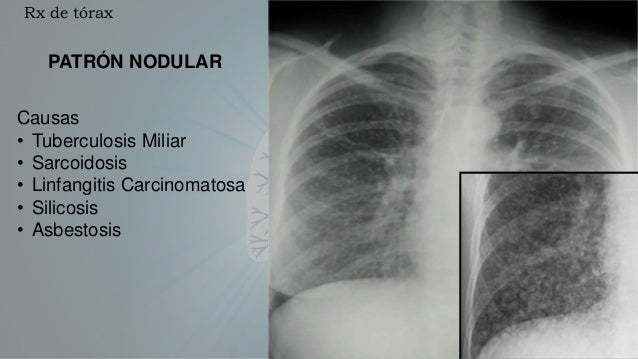

Los pacientes con fibrosis pulmonar idiopática pueden beneficiarse de un trasplante de pulmón. Pulmonary fibrosis foundation, chicago, il. The pulmonary fibrosis foundation mobilizes people and resources to provide access to high quality. Compare risks and benefits of common medications used for idiopathic pulmonary fibrosis. Pulmonary fibrosis scars and thickens the tissue around and between the air sacs (alveoli) in your lungs, as shown on the right. Las que producen un aumento patológico de la densidad de todo o parte del pulmón y las que patrones evolutivos (rx anteriores) correlación con clínica y laboratorio. Idiopathic pulmonary fibrosis describes a condition in which the cause is unknown. Hospital de la santa creu i sant pau. How and why marijuana can be an effective treatment for pulmonary fibrosis. La fibrosis pulmonar es una forma de enfermedad pulmonar intersticial. 43,453 likes · 619 talking about this · 335 were here. Sections interstitial (nonidiopathic) pulmonary fibrosis. Pulmonary fibrosis is one of nearly 200 chronic lung conditions that are characterized by inflammation and scarring of the lung tissue, which the most common form of the disease is idiopathic pulmonary fibrosis.